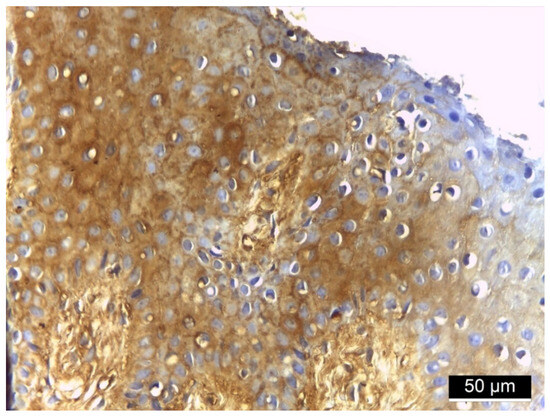

3.3. MMP-2 Immunoreactivity

4.2. MMP-2 Immunoreactivity